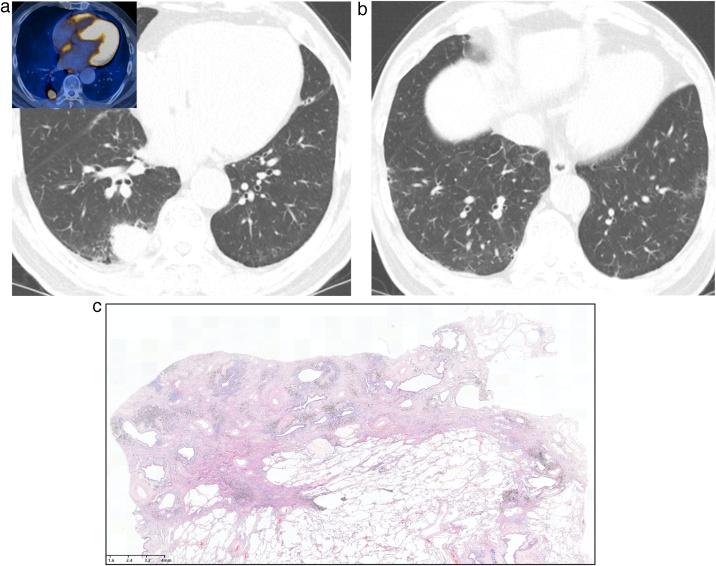

Interstitial lung abnormality (ILA) and nonspecific interstitial pneumonia (NSIP).

This review article aims to address mysteries existing between Interstitial Lung Abnormality (ILA) and Nonspecific Interstitial Pneumonia (NSIP). The concept and definition of ILA are based upon CT scans from multiple large-scale cohort studies, whereas the concept and definition of NSIP originally derived from pathology with evolution to multi-disciplinary diagnosis. NSIP is the diagnosis as Interstitial Lung Disease (ILD) with clinical significance, whereas only a part of subjects with ILA have clinically significant ILD. Eventually, both ILA and NSIP must be understood in the context of chronic fibrosing ILD and progressive ILD, which remains to be further investigated.